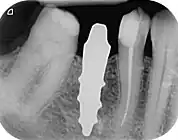

RAIs are custom made to perfectly fit the tooth socket of a specific patient immediately after tooth extraction. Therefore every implant is unique. As an optimised root-form it is much more than a simple 1:1 replica of a tooth. Since it exactly fills the gap left after the tooth is extracted, surgery is rarely needed. The implant can be produced from a copy of the extracted tooth, an impression of the tooth socket, or from a CT scan or CBCT scan.[3] The advantage of a CBCT scan is that the implant can be produced before extraction. With the former methods, it takes one or two days to fabricate an implant.

Technique[1]

Treatment consists of three steps:

- Obtain the 3D form of the tooth to be replaced. This is done either through careful tooth extraction and scanning of the root, taking an impression of the tooth socket, or a pre-op CBCT scan. The root analogue implant is produced using modern CAD/CAM technology, based on the Principle of Differentiated Osseointegration;

- Atraumatic extraction of the hopeless tooth;

- Placement of the root analogue implant by tapping it in. In general, no surgery is necessary. In particular, no sinus lift or invasive surgery is ever necessary. The implant is placed immediately if it has been produced beforehand from a CBCT scan, or the next day if root has to be scanned or an impression of the socket is used. A protective splint is fitted to protect the implant during the healing period.

Recovery time is very fast as neither soft nor hard tissue is traumatised. Typically, even the day after implant placement there is no swelling, bruising or pain. After 8–12 weeks' healing period, the final crown may be fitted by a family dentist.